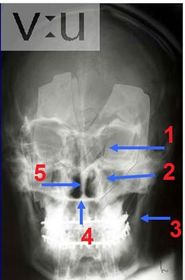

identify.. 1) cavity of orbit 2) maxillary air sinus 3) mandibular ramus 4) hard palate 5) nasal septum